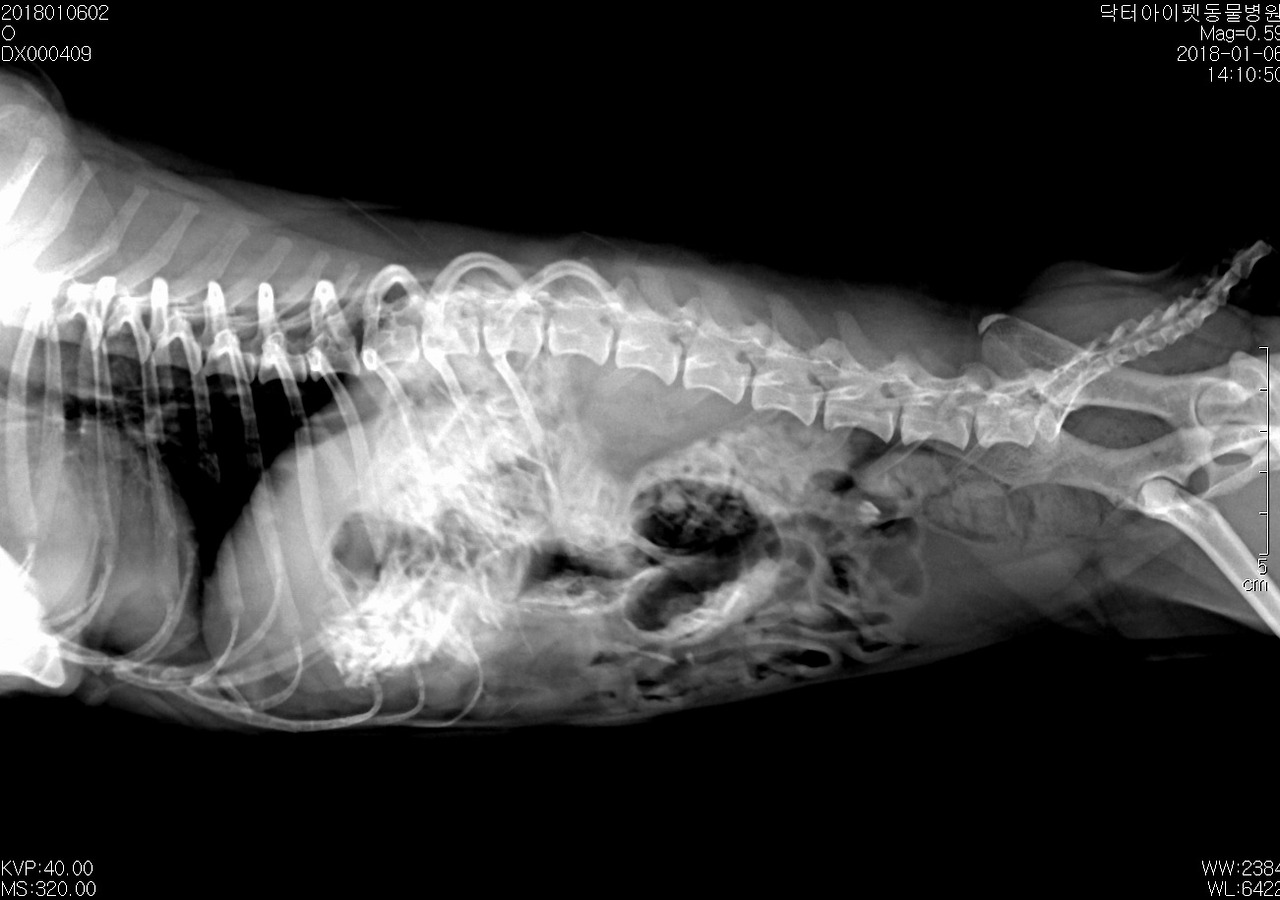

엑스레이를 찍어봤다. 위 한 가득 치킨 뼈가 차있었다. 일반적인 케이스라면 수술을 우선적으로 고려했을 거다. 다행스럽게도 띠띠는 침을 많이 흘리거나 출혈성 구토, 혈변 등의 증상이 없었다. 절대 금식을 당부하고 3일 통원치료를 계획했다. 72시간 정도 경과하면 대부분 섭취한 음식물은 소화되기 따름이다. 기대한 대로 대부분 소화되어 대변으로 배출되었다.

통원 1일, 2일, 3일차 방사선 사진. 다행이었다. 뼈는 모두 소화되고 배출되었다.